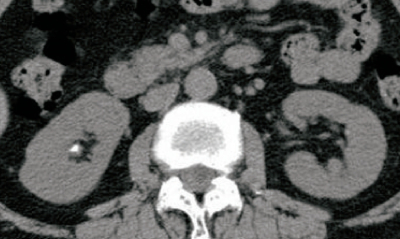

血液生化学所見:アルブミン 3.7 g/dL、Ca 11.2 mg/dL、P 2.4 mg/dL、副甲状腺ホルモン〈PTH〉 170 pg/mL( 基準 10~60)。腹部CTを別に示す。